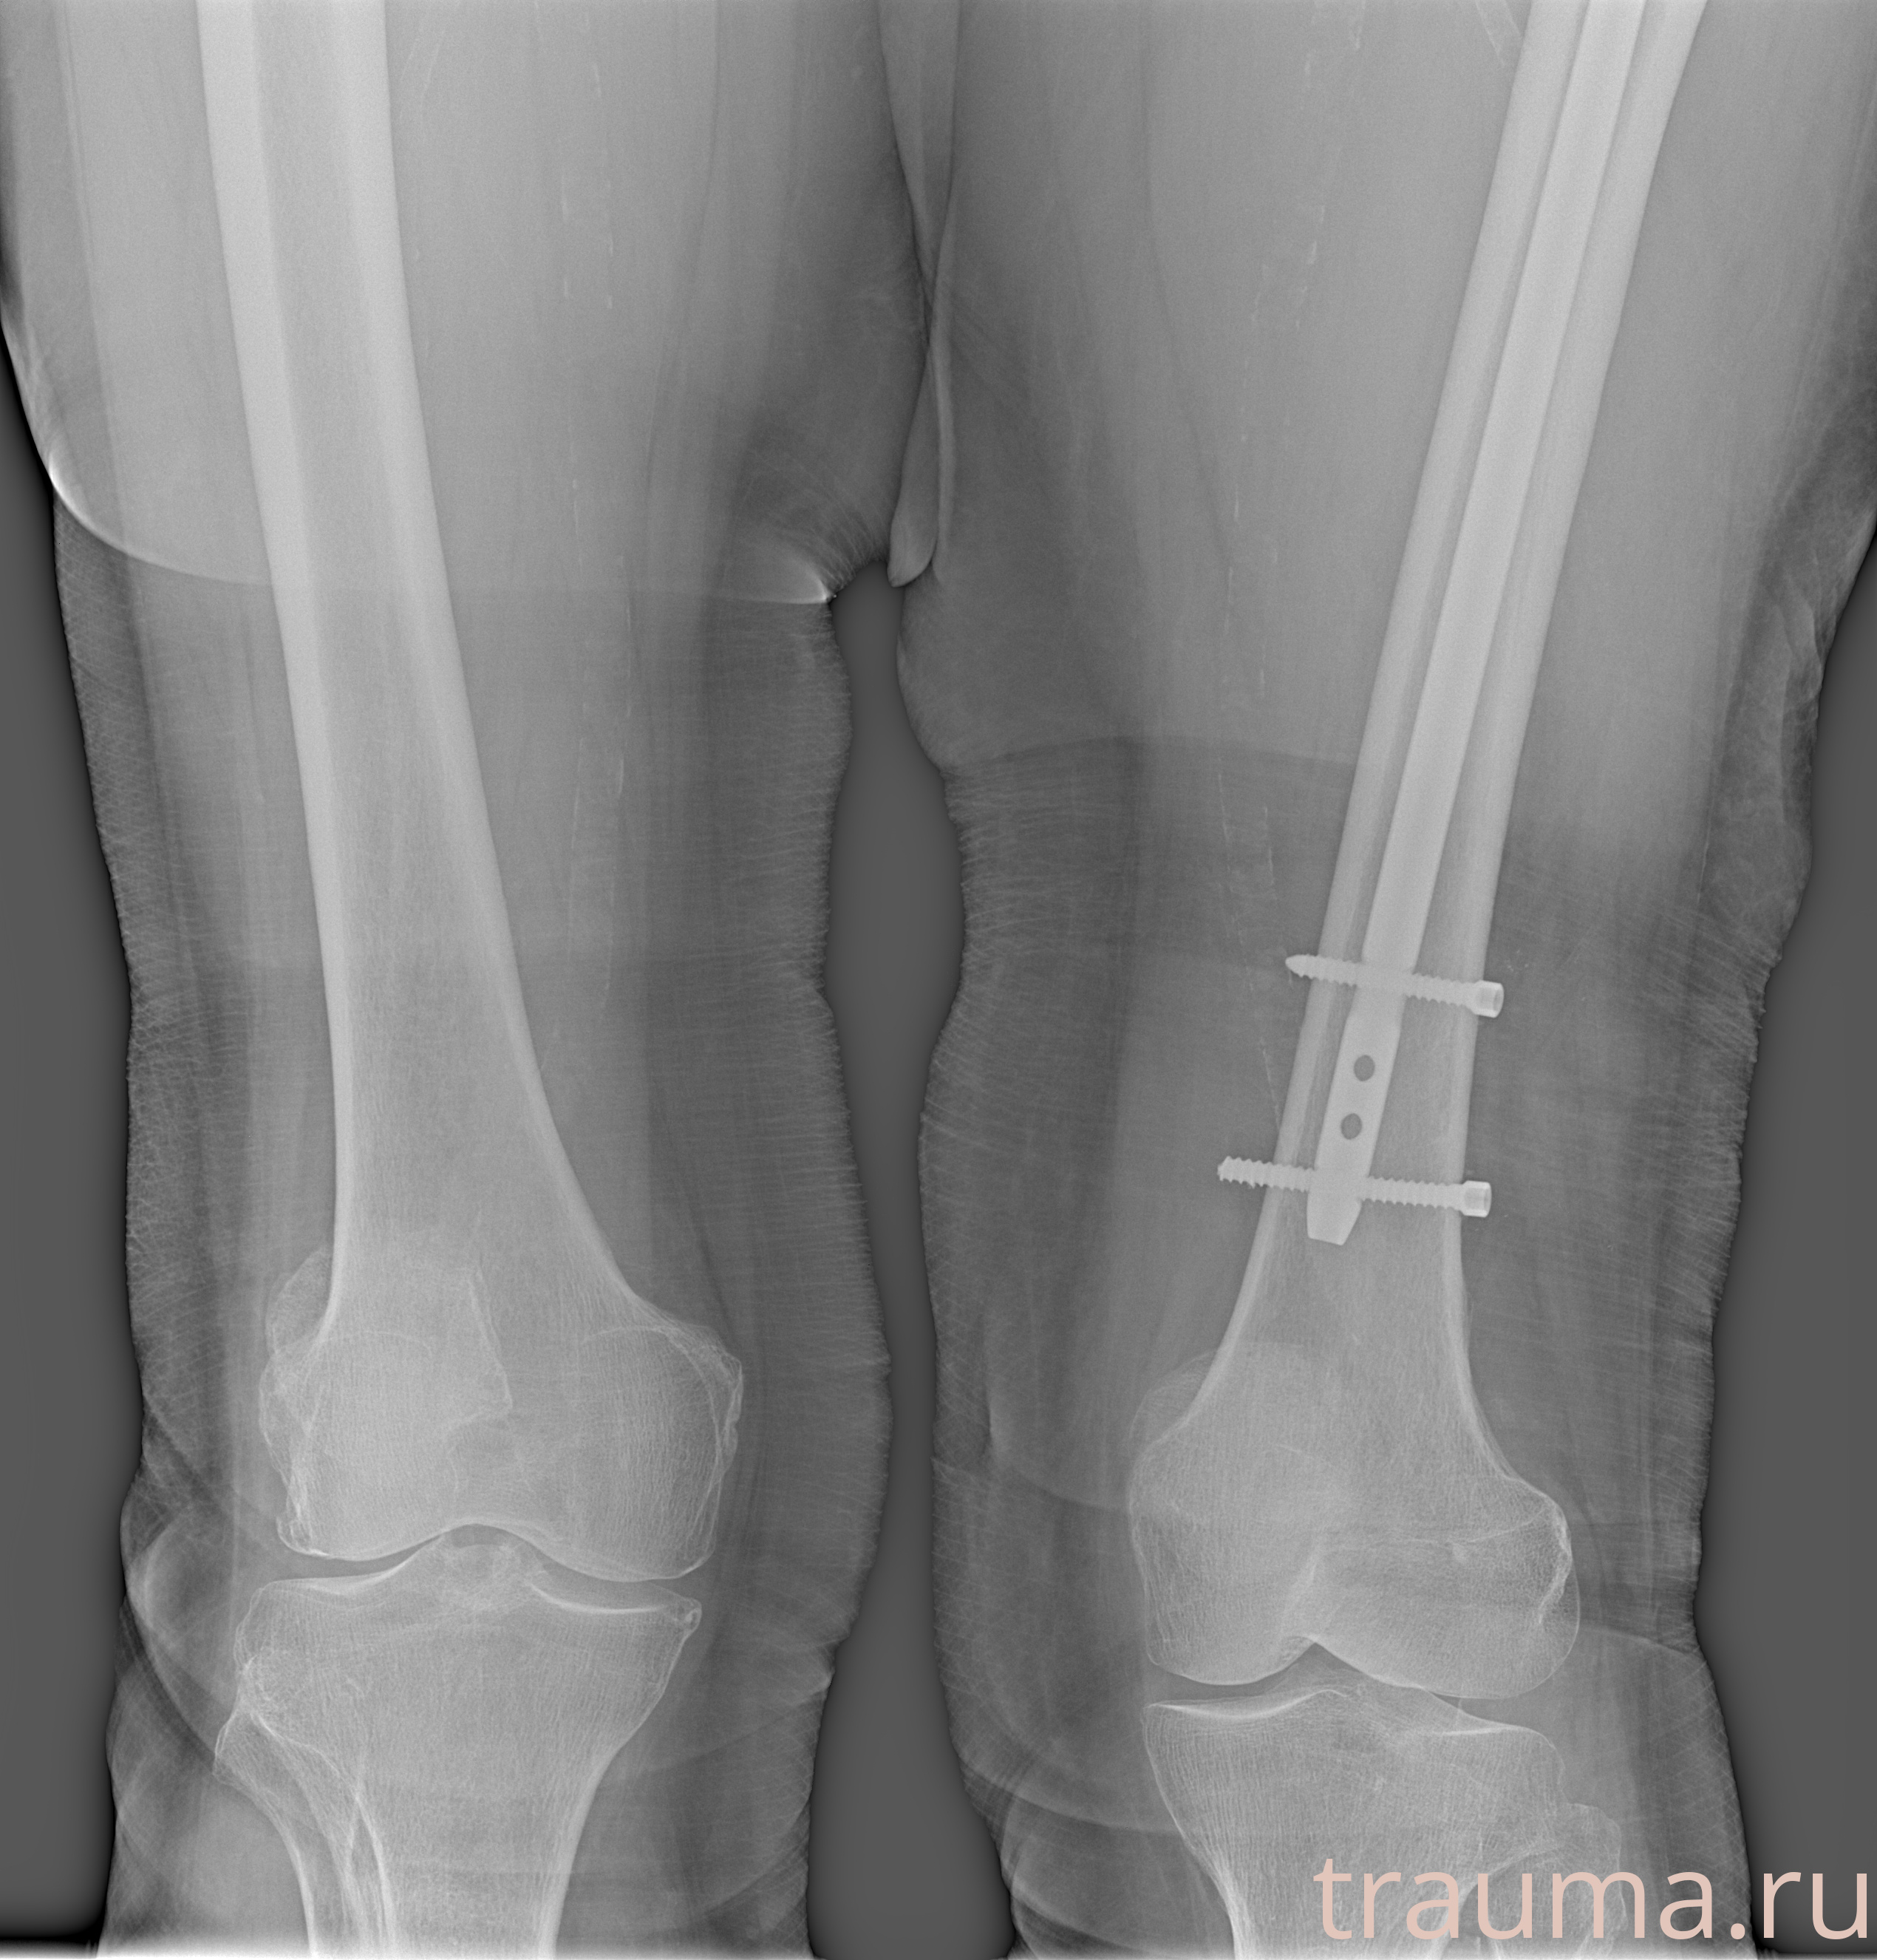

Рентгенограммы

Рентген на дому: по вашему адресу приезжает врач-рентгенолог, травматолог-ортопед с мобильным рентгеновским аппаратом, проводит диагностику травмы или заболевания, делает необходимые рентгенограммы, дает рекомендации по дальнейшему лечению. Получить качественные снимки в домашних условиях возможно благодаря уникальной методике, разработанной МосРентген Центром для института  Склифосовского